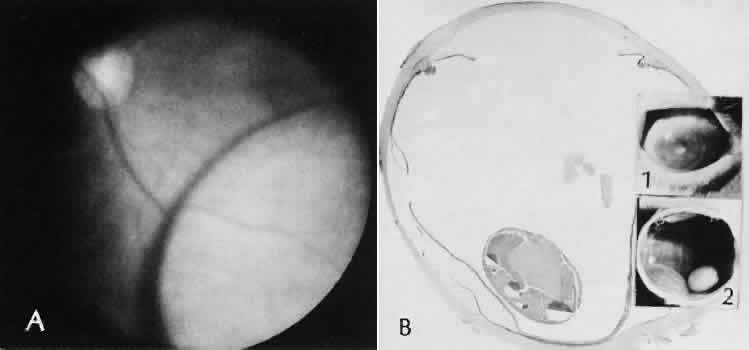

Expulsive choroidal hemorrhage (Fig. 30) is a rare catastrophic complication often resulting in total loss of the eye.93 The site of hemorrhage is probably a sclerotic choroidal arteriole where the vessel crosses the suprachoroidal space from the scleral canal. The sudden hypotension after surgical penetration of the globe causes a bending and then a rupture of the arteriole.94 Although most hemorrhages are massive and immediate, they occasionally are delayed, and some may not occur for days or weeks after surgery. Delayed choroidal hemorrhage may occur at the time of corneoscleral suture removal,95 because of clinically unapparent wound dehiscence or as a result of perforation of a corneal ulcer.

Fig. 30. A case of expulsive choroidal hemorrhage. A. Expulsive choroidal hemorrhage occurred 3 weeks after cataract surgery at the time when a limbal suture was removed. The intraocular pressure was reduced enough to allow shearing forces in the superficial choroid to tear an arteriole resulting in a high-pressure hemorrhage. B. In another case enucleated shortly after cataract extraction because of expulsive hemorrhage, accumulated blood can be identified in the suprachoroidal space. Because of the loose attachment of the choroid to the sclera, all intraocular contents were displaced toward the cataract wound. (Hematoxylin-eosin stain; × 3.)

Histologically, massive choroidal hemorrhagic detachment is associated with a retinal detachment. The retina and choroid may herniate through the scleral wound. A ruptured ciliary artery may be found in the suprachoroidal space.